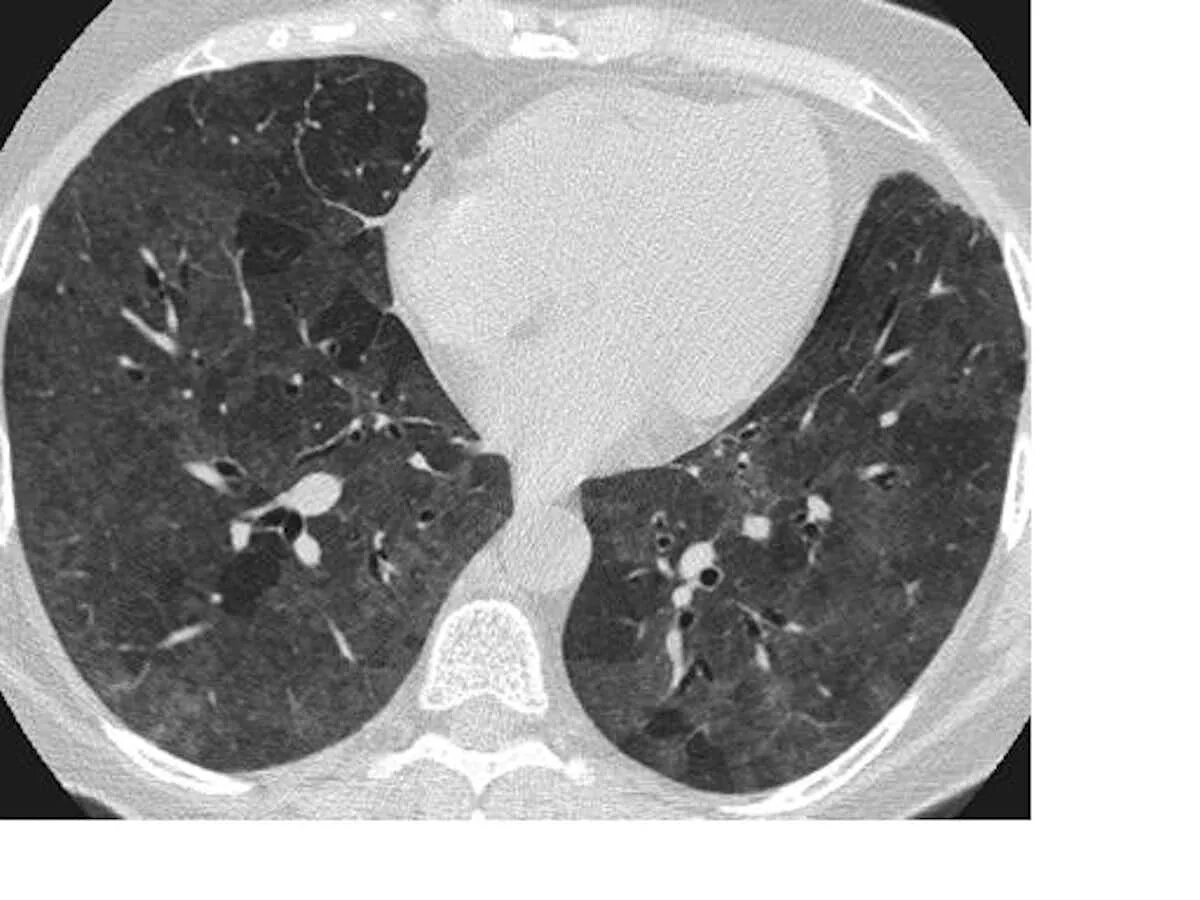

Мозаичная перфузия